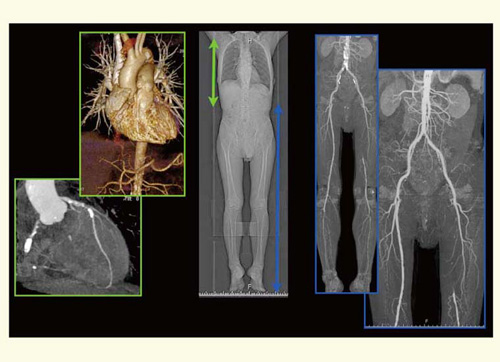

2010年1月,奈良県立医科大学病院にDefinition Flashが導入された。われわれは,閉塞性動脈硬化症(ASO)に対するスクリーニングでは上行大動脈や冠動脈の評価も行うようにしているが,Flash SpiralとDual Energyの使い分けを検討中である。現状では,胸部領域から腎動脈レベルにかけてはFlash Spiralを用い,腎動脈以下からはDual Energyを使って評価するようにしている。それによって,石灰化の強い症例でも評価が可能になっている(図9)。

図9 Flash SpiralとDual Energyの使い分け